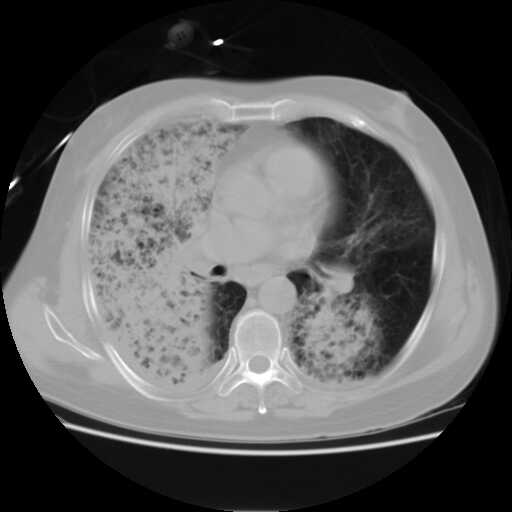

2008.8.17ct定位片

2008.8.17ct

病变从8.11-8.17明显改变,增多,以蜂窝状改变为主,类蜂窝肺,似弥漫性肺泡癌,但是病变进展太快,不符合弥漫性细支气管肺泡癌。因此考虑为特殊微生物感染,多以霉菌类常见,建议细菌微生物学检查。

疑点二:影象表现怪异,大片阴影内见多发筛孔征,如何解释.

结合临床慢支炎肺气肿,肺心病病史,三次胸片观察可见病情发展变化迅速,病情凶险,考虑多重感染伴ards.